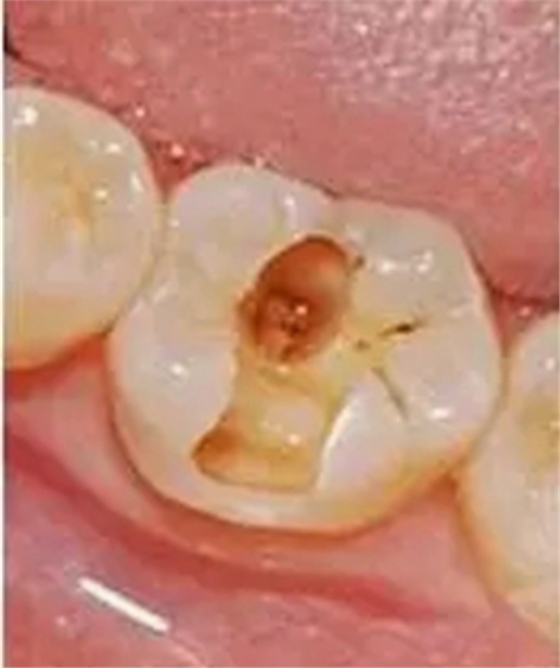

3,深齲

齲壞已達牙本質(zhì)深層,一般表現(xiàn)為大而深的齲洞,或入口小而深層有較為廣泛的破壞,對外界刺激反應較中齲為重,但刺激源去除后,仍可立即止痛,無自發(fā)性痛。